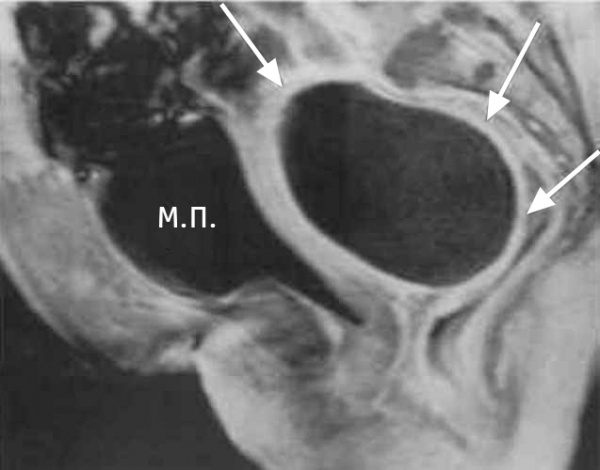

16 Диагностика Рентгенологическая картина мало информативна. Большую роль в диагностике играют ультразвуковое исследование, магнито резонансная томография. При ректальном исследовании выявляют зияние сфинктера прямой кишки, дряблость стенок ампулы, нависание передней стенки ампулы.

Абсцесс дугласова пространства – инкапсулированный гнойный очаг, расположенный в маточно-прямокишечном (прямокишечно-пузырном) углублении малого таза. Клиника характеризуется неспецифическими проявлениями (интоксикацией, фебрильной температурой, ознобами) и местной симптоматикой (болью в нижних отделах живота, дизурическими явлениями, частыми позывами на дефекацию). Диагностика включает ректальное и вагинальное (у женщин) исследование, УЗИ малого таза, КТ, пункцию гнойника через прямую кишку или задний свод влагалища. Лечение абсцесса дугласова пространства заключается в его вскрытии через прямую кишку или влагалище, дренировании и санации, проведении антибиотикотерапии.

Пальпаторно определяется болезненность в области малого таза, локальное напряжение мышц, положительный симптом Щёткина — Блюмберга. При ректальном или влагалищном исследовании выявляется болезненный тугоэластический инфильтрат с размягчением и флюктуацией в центре. У женщин абсцесс дугласова пространства пальпируется выше шейки матки, определяется нависание заднего свода влагалища.

КТ органов малого таза. На снимке: абсцесс, отграниченный стенкой (А), прямая кишка (R), матка (U), мочевой пузырь (B)

Для дифференциальной диагностики с тубоовариальным абсцессом у женщин проводится УЗИ малого таза; для исключения абсцесса предстательной железы у мужчин – УЗИ простаты.

В сложно дифференцируемых случаях может потребоваться выполнение компьютерной томографии, МРТ. Для окончательного распознавания абсцесса дугласова пространства прибегают к диагностической пункции гнойника под ультразвуковым наведением через прямую кишку либо задний свод влагалища. Полученное гнойное содержимое подвергается бактериологическому исследованию.